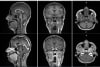

First-in-human contrast enhanced MRI images with GE HealthCare's mangaciclanol

MRI contrast agents enhance the visualization of abnormal structures or lesions during imaging procedures and help clinicians better distinguish between healthy and diseased tissue. Mangaciclanol is intended for general-purpose MR imaging and demonstrates comparable relaxivity (the ability to enhance signal intensity) to market-leading gadolinium-based agent, gadobutrol, with early clinical images suggesting similar diagnostic capability. Unlike gadolinium, which is a rare-earth metal, manganese is present in our food, and is an endogenous element, naturally occurring and autoregulated in the body. The macrocyclic ‘cage-like’ structure of mangaciclanol lessens the possibility of retention.